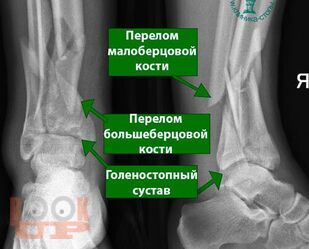

Современные принципы диагностики и лечения внутрисуставных переломов дистального отдела большеберцовой кости (переломы «пилона»)

Данное учебное пособие содержит подробное описание диагностики и тактики лечения переломов дистального метаэпифиза большеберцовой кости и возможности применения внеочагового и накостного методов лечения при данных видах переломов, а также описание послеоперационного ведения больных с данной патологией, возможные осложнения и сроки реабилитации после этого вида травмы.